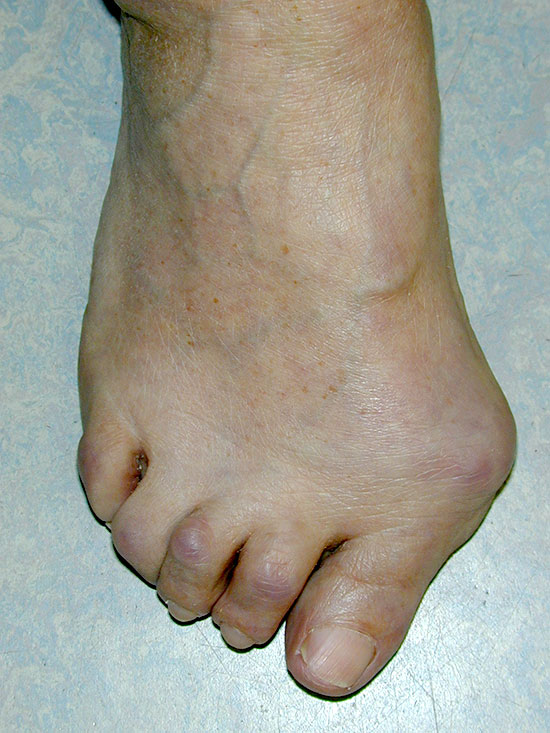

Im Verlauf kommt es durch Zerstörung des Kapsel-Band-Apparates und Sehnen zu Instabilitäten („loose type“) und durch Zerstörung der Gelenkflächen mit Bewegungseinschränkung („stiff type“) zu den typischen rheumatischen Veränderungen. Schlüsselgelenk für die Rückfußstabilität ist das Talonavikulargelenk. Die Lockerung des Kapsel-Bandapparates mit begleitender Insuffizienz der Tibialis-posterior-Sehne führt zum Tiefertreten des Taluskopfes und Verlust der medialen Längswölbung (rheumatischer Knick-Senkfuß). Im Subtalargelenk entsteht eine Valgusfehlstellung, oft begünstigt durch eine Valgusfehlstellung des Kniegelenkes. Verlust der Längswölbung und Medialisierung des Os naviculare führen zur Aufbiegung der Mittelfußknochen an DI (varisierend und supinierend) und DV (valgisierend und pronierend). Durch veränderte Sehnenzugrichtungen entsteht die Hallux valgus-Positionierung der Großzehe und Varisierung der Kleinzehe als Digitus quintus varus. Die Mittelfußköpfchen II-IV werden durch die Aufspreizung überlastet. Es kommt zur Metatarsalgie mit Hyperextension in den MTP und pathologischer plantarer Beschwielung sowie kontrakten Krallenzehen (Sabo D(ed). 2010).

Die klinische Untersuchung sollte im Gehen, Stehen und Liegen durchgeführt werden. Im Gehen sind Gangbild und Abrollvorgang zu beobachten. Im Stehen erfolgt dann die Bestimmung der Beinachsen, Feststellung einer einseitigen Muskelminderung (z.B. der Wadenmuskulatur als Ausdruck einer Schonung) und die Beurteilung der Rückfußachse. Beim Erwachsenen sind 5-10° Valgusstellung physiologisch, die im Zehenstand bei suffizienter Tibialis posterior-Sehne in eine leichte Varusposition übergeht. Des Weiteren werden im Stehen Längs- und Querwölbung (Breite des Vorfußes zwischen MTPI und V) des Fußes beurteilt, der Valguswinkel zwischen Großzehe und Fußlängsachse gemessen sowie Zehendeformitäten wie Krallen-, Hammerzehen sowie eine Überkreuzung von Zehen festgestellt. Im Liegen können die Bewegungsausmasse der Gelenke, die Beschwielung des Fußes, Druckstellen, trophische Veränderungen der Haut und Fußnägel erfasst werden. Bei der Palpation der Gelenke und Sehnen sind Schwellung, Überwärmung und Schmerzhaftigkeit festzustellen.